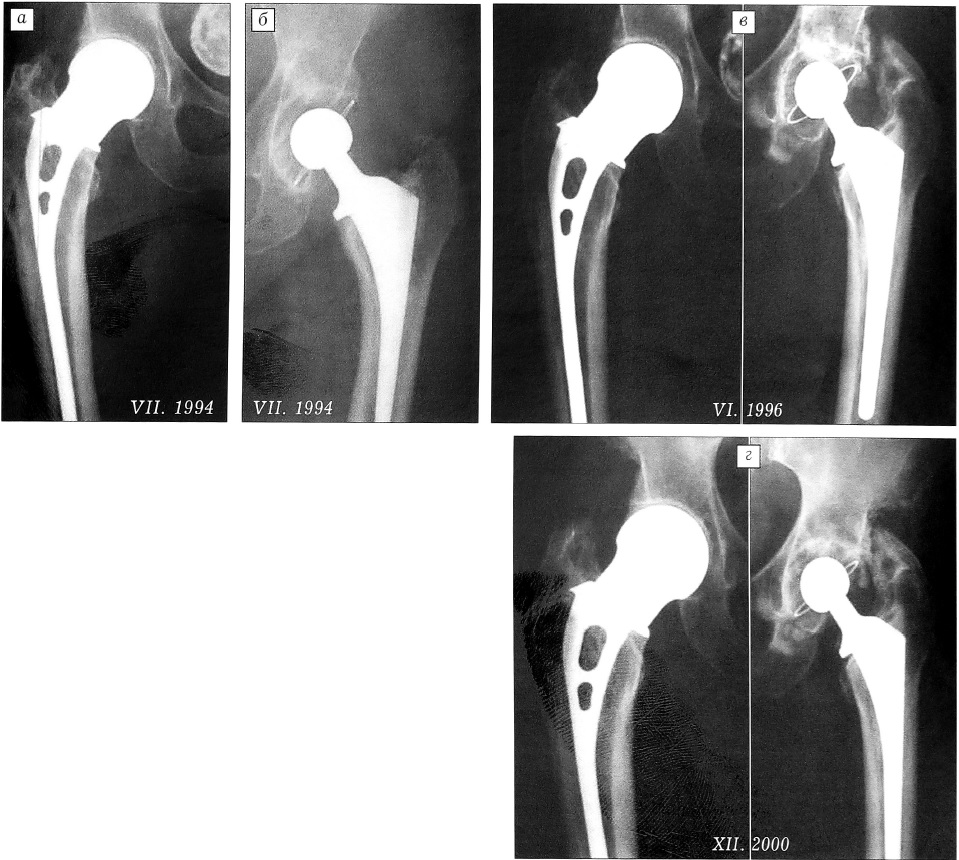

Использование биополярных эндопротезов современных конструкций также далеко не всегда предотвращает развитие протрузии головки в вертлужную впадину, наиболее часто это связывают с остеопорозом (рис. 2). Вместе с тем в ряде случаев монополярные эндопротезы служат в течение длительного времени без признаков развития нестабильности или протрузии и переживают современные тотальные эндопротезы цементной фиксации, установленные с помощью техники цементирования II генерации, наиболее распространенной в нашей стране (рис. 3).

Рис. 2. Протрузия биполярной головки в вертлужную впадину в течение 2 лет.

Рис. 3. Больная А. 86 лет. В 1992 г. произведено эндопротезирование правого тазобедренного сустава протезом Мура—ЦИТО, в 1994 г. — эндопротезирование левого тазобедренного сустава тотальным эндопротезом с фиксацией на костном цементе. а — через 2 года после эндопротезирования правого, б — непосредственно после эндопротезирования левого тазобедренного сустава; в — изменений со стороны гемипротеза через 4 года после установки нет, отмечается «проваливание» цементной ножки Вi-metriс через 2 года после операции; г — положение гемипротеза через 8 лет после операции не изменилось, положение цементного эндопротеза через 6 лет стабилизировалось.